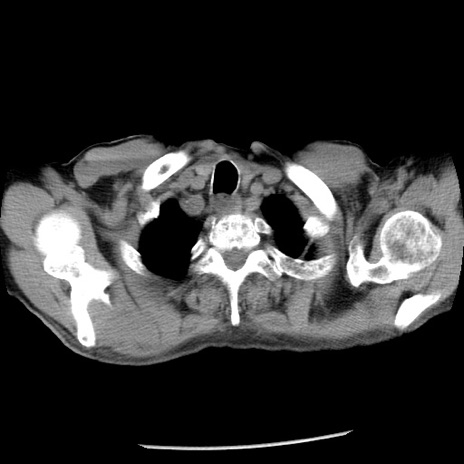

冠状断像

症例26(横断像)

【症例】80歳代男性

【主訴】嘔吐

【現病歴】昨晩2回嘔吐あり、今朝になっても嘔吐あり。来院。

【既往歴】胃潰瘍

【身体所見】意識清明、BT 37.6℃、BP 166/95mmHg、HR 100bpm、SpO2 97%、腹部:平坦・軟、腸蠕動音聴取良好、圧痛なし。

【データ】WBC 21900、CRP 1.46